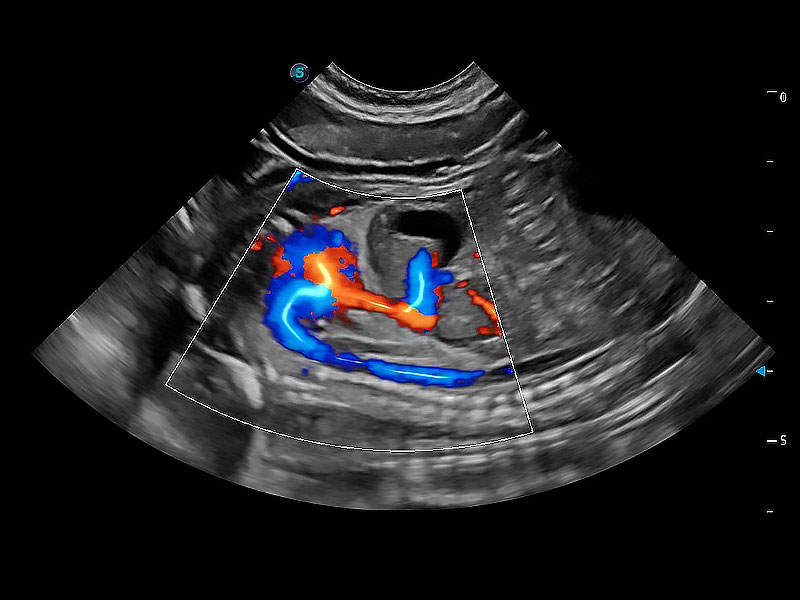

• Bright Flow 立体血流成像

在传统二维血流成像的基础上,呈现血流的立体感,具有动感的生命力之美。即便是微小的血管也能轻松应对,提高了血流的视觉敏感性。

(犬)胎儿主动脉弓立体血流

(犬)胎儿四腔心